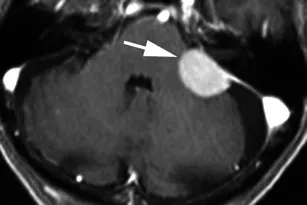

70岁头痛女性患者。增强冠状位T1加权序列显示右中央前回受压(箭头),病灶轻度不均匀强化,呈宽基底硬脑膜附着,周围显着血管源性水肿。T2加权序列呈高信号(相对于灰质)。术后病理证实为原发性乳腺癌腺癌转移。